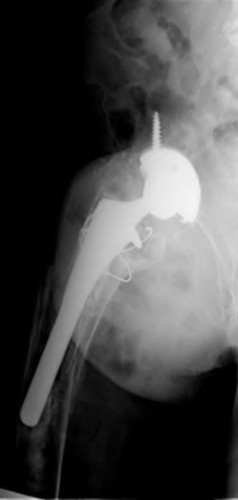

A 72-year-old female falls and sustains a periprosthetic femur fracture around her cementless total hip arthroplasty. Radiographs reveal a fracture extending just distal to the tip of the stem. The stem is radiographically loose, but there is excellent proximal and distal bone stock. According to the Vancouver classification, what is the fracture type and the recommended surgical treatment?

Explanation